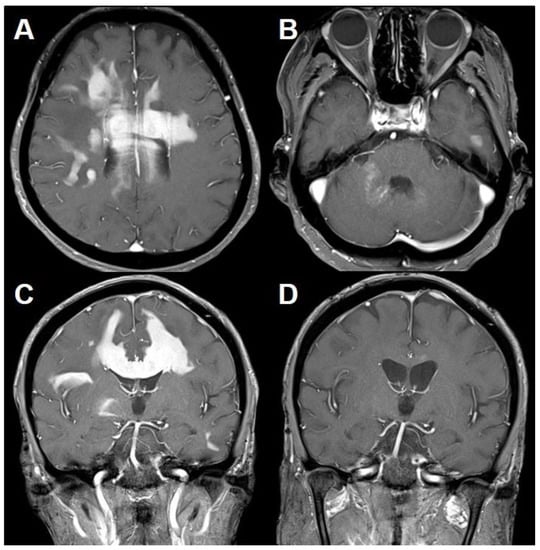

Figure 3.

MRI of primary central nervous system lymphoma (PCNSL) following the preceding inflammatory lesion. T1-weighted MRI with gadolinium (A–C) showing homogeneously enhancing lesions in the bilateral cerebral hemisphere and corpus callosum with punctate enhancing lesions in the right middle cerebellar peduncle. Follow-up T1-weighted MRI with gadolinium (D) demonstrating complete resolution of the lesions after chemotherapy therapy.

Neuro-navigation guided burr hole biopsy targeting the right frontal lobe revealed diffuse large B-cell lymphoma (Figure 4). A subsequent systemic evaluation provided no evidence of a systemic lymphoma. She was treated with methotrexate chemotherapy and cytarabine chemotherapy due to methotrexate-induced diabetic insipidus. This treatment provided clinical improvement and nearly complete remission of the lesions on subsequent brain MRI (Figure 3D). Thirty-five months after the initial attack, she suddenly developed right hemiparesis and cognitive impairment. Brain MRI showed homogenously enhancing lesions in the left basal ganglia and pons along the corticospinal tract. She refused further treatment and died at 38 months after the disease onset.